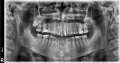

Прошу посмотреть мои зубы и сказать предварительно — где нужны пломбы, а где коронки?

Если Вы выложите снимок, я Вам с удовольствием помогу.